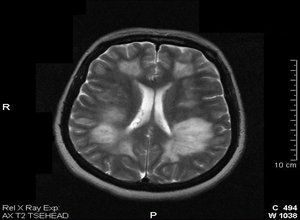

腦脊液正常或表現為細胞、蛋白增多,病毒PCR檢測陰性,OB多為陰性,或一過性陽性,24小時鞘內IgG合成率增高。影像學特點:MRI是最重要的診斷工具,T2和FLAIR相表現為片狀的邊界不清的高信號,多發、雙側不對稱。病灶累及廣泛,包括皮層下、半卵圓中心、雙側半球的灰白交界、小腦、腦幹和脊髓。丘腦和基底節常受累,病灶多不對稱。胼胝體和腦室旁白質較少受累,這些部位病變更易出現在MS。11-30%的患者可出現強化病灶。

ADEM的頭顱MRI病灶有四種形式:多發小病灶(<5mm),瀰漫性大病灶可類似腫瘤樣伴有周邊水腫和占位效應,雙側丘腦病變,出血性病變,四種形式可單獨出現,也可合併出現。有脊髓症狀的患者80%脊髓MRI可發現病灶,可為局灶或節段性,但多數為較長脊髓節段(>3)甚至為全脊髓。隨訪MRI發現37-75%的患者病灶消失,25-53%的患者病灶改善,IPMSSG建議ADEM患者發病5年內應至少進行2次隨訪以排除MS和其他疾病。